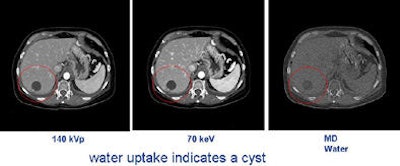

In the hands of researchers, dual-energy analysis of images could potentially help distinguish cysts from cancers and possibly even malignant from nonmalignant lesions in the lungs, colon, solid organs, and blood vessels.

"We have actually subtracted out iodine and water in soft tissues. If you measure the energy, you can actually discern where cysts and cancers are," Smith said.

The interpolation process, performed by the scanner's software, can estimate 101 energy levels that fall between high and low kVp levels pulsed during scanning, Stahre said. The interpolation function is precise, he said, because it is based on known attenuation curves for various materials. Therefore, by comparing the same point on two curves, many materials such as water and iodine can be distinguished, potentially enabling the differentiation of soft tissues. For example, early research has shown that a liver cyst that absorbs water can be distinguished from a tumor, which absorbs iodine.

"You've got these small pancreatic cystic lesions … can you better define those? You've got the indeterminate renal lesion, is it a cyst or a solid tumor? What about detecting smaller tumors in screening for liver disease?" Foley said. In the lungs, there is potential for better assessing lung nodules in serial studies.